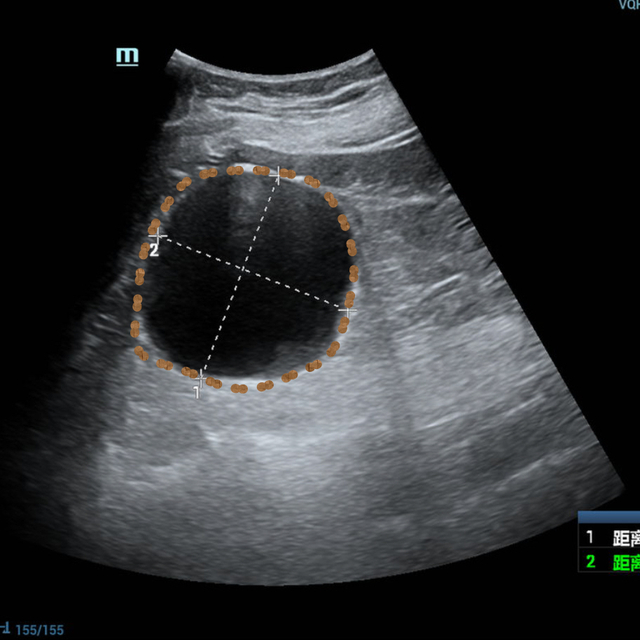

无独有偶,家住城东的赵老先生时感右腰酸胀,到附近医院检查后发现右肾有一个7.0*6.4cm的巨大囊肿,这成了老赵的一块心病。儿女们也为老父亲的囊肿四处求医,最后慕名来到昆山市中医医院超声介入门诊寻求帮助。

▲患者超声影像

超声介入张轶亮主治医师了解老赵的病情后立刻为其超声检查,发现右肾囊肿确实很大,已经压迫了周围肾组织。

考虑到老赵年事已高,行动不便,王晓明副主任医师当即电话联系泌尿外科,安排其住院,并行CTU(尿路造影)、血凝等术前常规检查,第二日在局部浸润麻醉下进行超声引导下肾囊肿穿刺抽液硬化治疗。